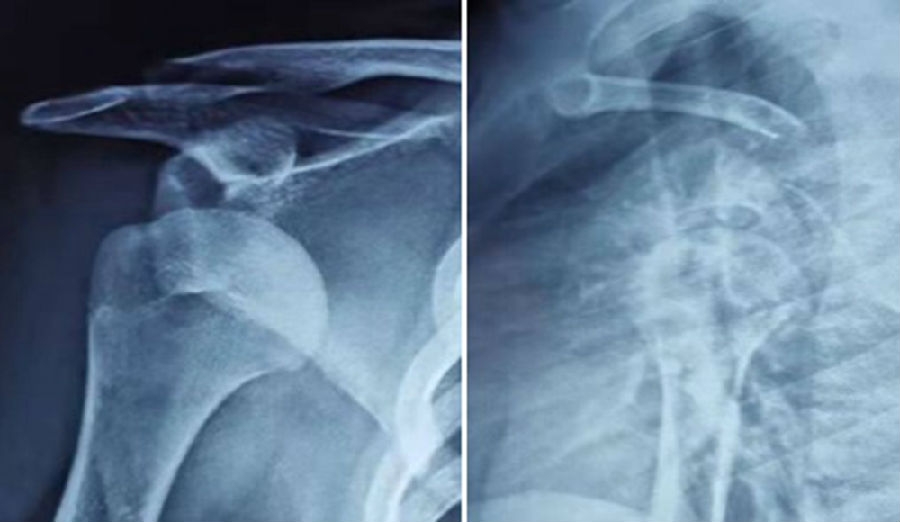

典型病例,王XX,男性,15岁。主诉右肩外伤疼痛、活动受限1月。既往半年前有肩关节脱位病史。

图37 既往肩关节脱位时,急诊所拍的X线片

图38 复位后的肩关节CT

视频6-7(拼在一个画面里,左右并排) 术前查体,ISIS评分6分